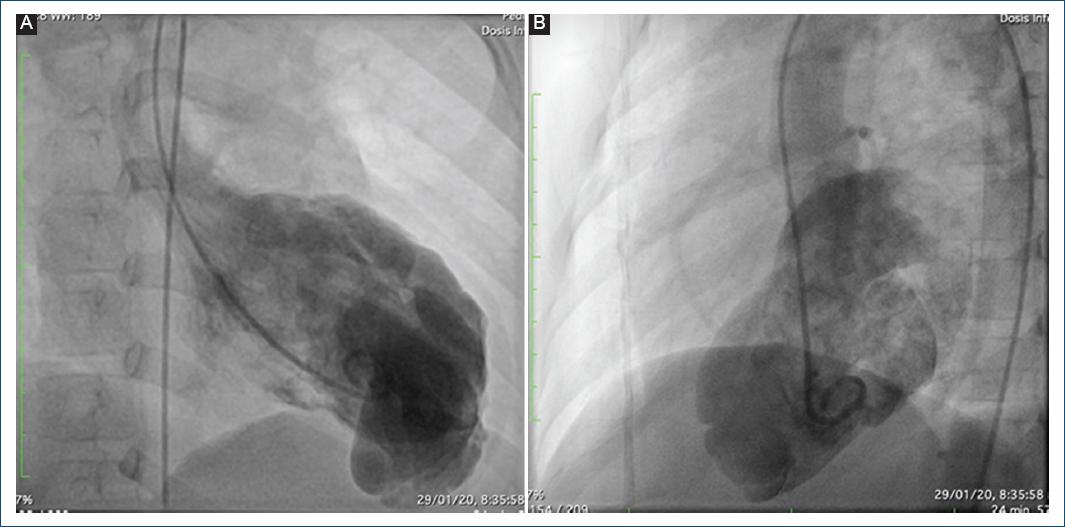

Se trata de un paciente remitido a una institución de alto nivel de complejidad en la ciudad de Medellín, Antioquia, Colombia, a los 20 días de vida, producto de un embarazo a término, con adaptación neonatal espontánea, peso y talla adecuados para la edad gestacional, con paraclínicos infecciosos normales y diagnóstico prenatal de aneurisma ventricular izquierdo (AVI) de 1.6 mm de diámetro, confirmado por ecocardiografía y RM cardiaca posnatal, con ausencia de endocardio asociado, hipocinesia grave, con función ventricular normal y extrasistolia ventricular leve, unifocal, bigeminada, con una carga arrítmica total no significativa del 0.6%. El caso fue llevado a reunión médico-quirúrgica, en la que se decidió realizar un cateterismo diagnóstico, el cual mostró arterias coronarias normales, con divertículo del ventrículo izquierdo (DVI) gigante (Fig. 1).

Figura 1 A: ventriculografía que muestra un aneurisma en el ápex cardiaco. B: vista lateral del aneurisma.